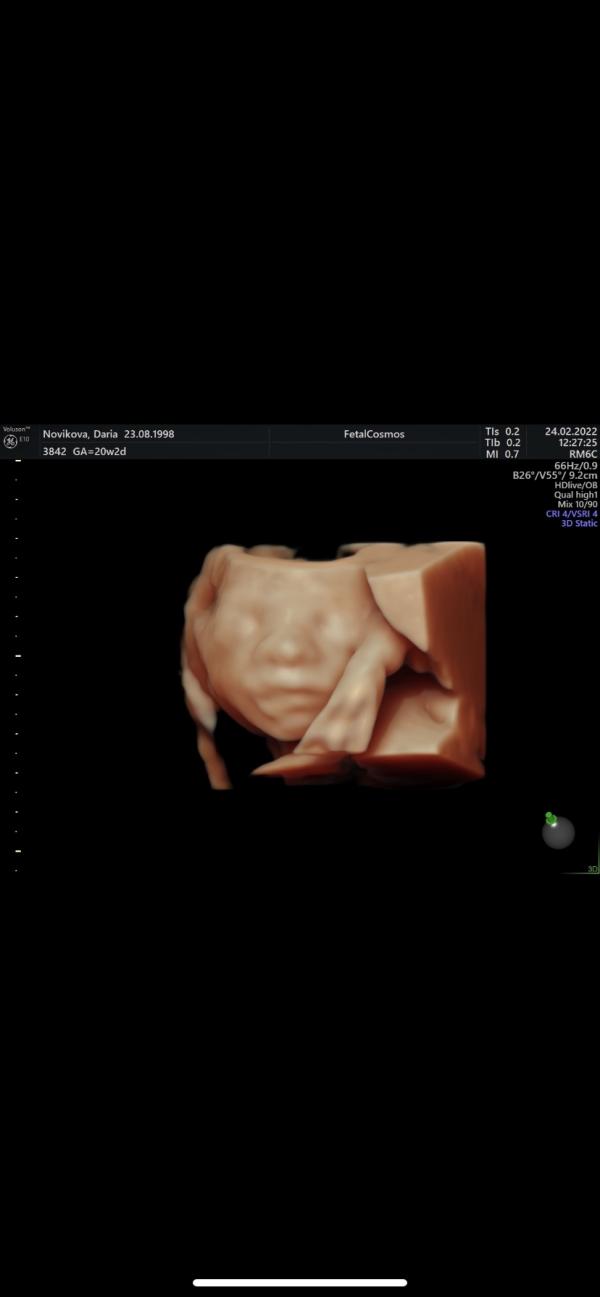

Был сегодня второй скрининг. Малыш постоянно позировал для фото, но нужными частями не поворачивался. 😁 по этому пробыли в кабинете около часа. Все же лучше, чем в прошлый раз (скрининг длился 2,45ч, малыш не хотел поворачиваться так, как нужно)

Да 😞 мне ещё очень грубо делали узи, живот болел после него. Растормошить пытались ребёнка :(